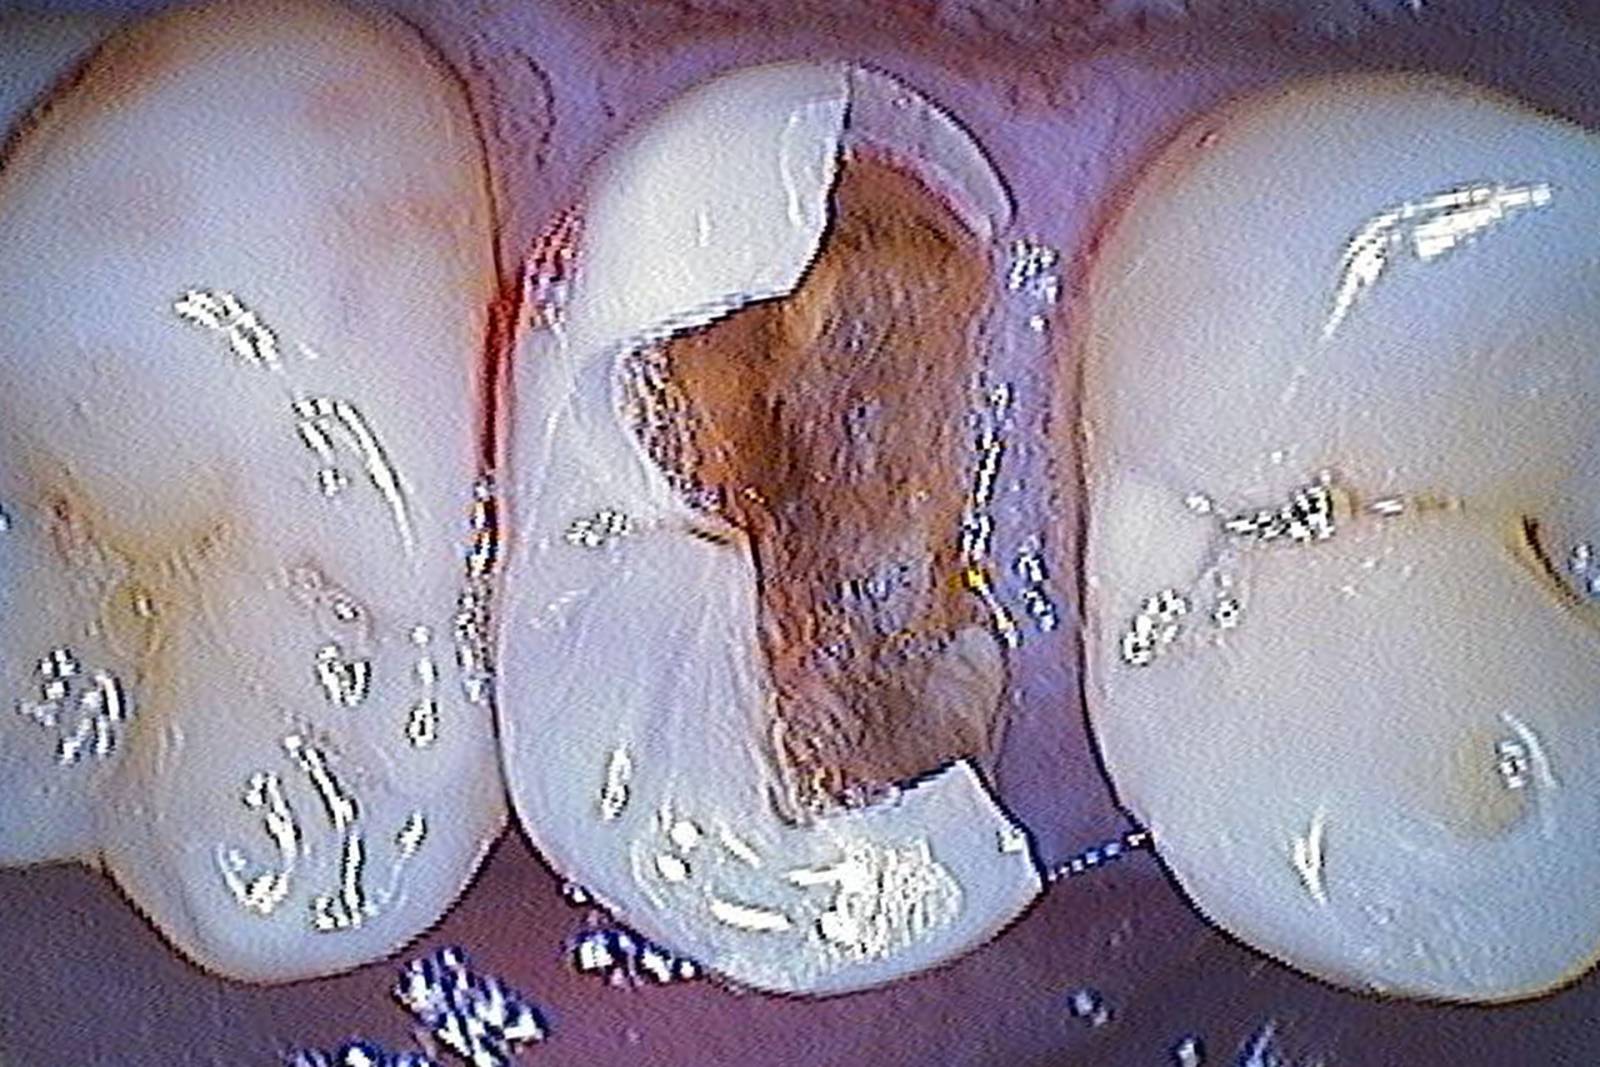

Before: Fractured ceramic restoration made from a leucite-reinforced glass-ceramic after a clinical service time of 12 years.

After: Chairside-fabricated restoration made from an advanced lithium-disilicate ceramic CEREC Tessera.